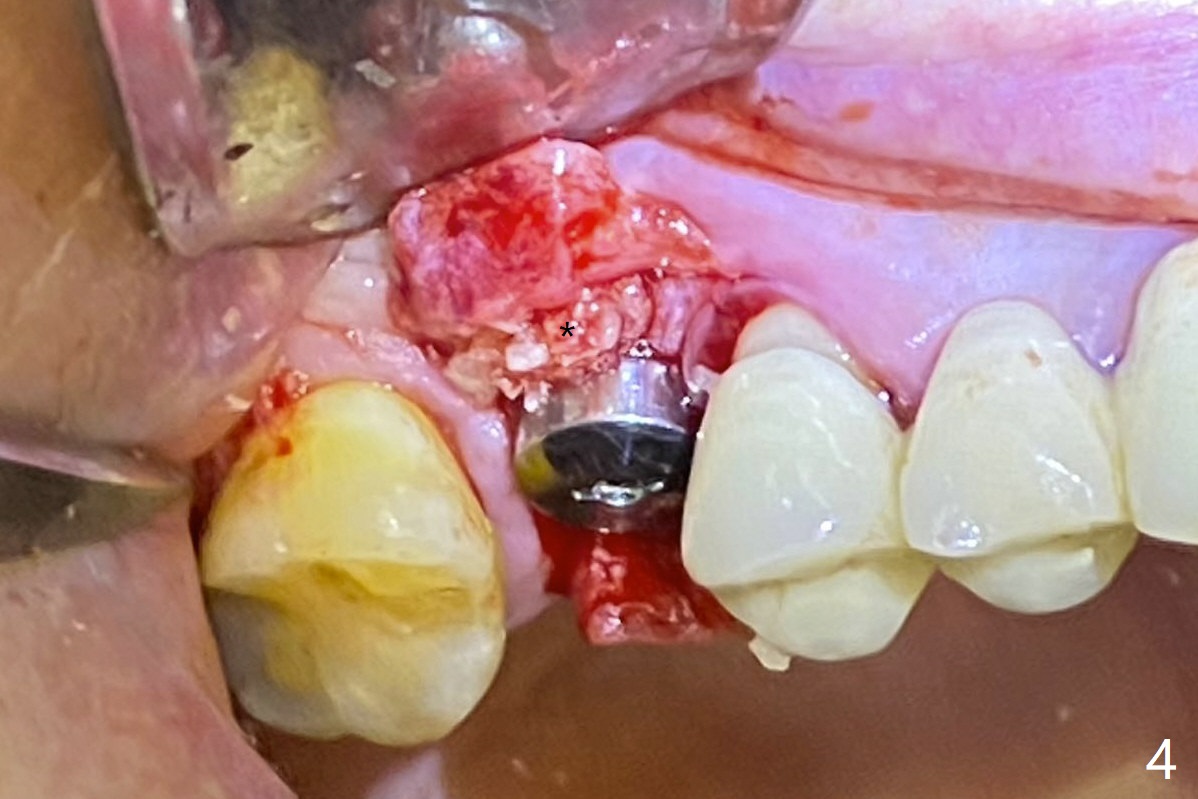

我们将使用粘性骨块做上颌窦内提升。抽血,一个红试管(含促凝剂),离心每分钟1500转,3分钟,提取上清液,与异体骨混合,几秒钟骨粉就开始凝聚(录像)。右上六缺牙区切开,开始用2毫米钻头钻洞,深度4毫米,如何使用2.8,3.6毫米园钻头(对上颌窦膜安全),4-6 毫米深,由于上颌窦底板是斜型,没有突破感。接着想利用粘性骨块和报废植体,把骨块送上去,这时骨块相当硬,必须事先剪成适当大小,然后用报废植体(4x10毫米)慢速推上去(录像2,图一(*骨块))。数次提升后,放置4.5x8.5毫米正式植体(图二),调整植体深度(图三:<),在稍微暴露植体表面放置骨块(图四:*)。其实愈合基台没有就位(图五:>),更换后没这个问题(图六)。

提取上清液后,红管再次离心,同样速度,5分钟,便形成PRF(胶状,上面黄色部分,图七),由于试管在离心机放置角度缘故,PRF与下面红血球部分(深色)交界处是一个斜面,制作PRF膜前,必须在交界处下面剪(图八白斜线),因为在交界处有效成分浓度最高,请看录像(虽然剪的太高些)。制作完毕的PRF膜可以覆盖图四骨块表面,但是用于图一之后,塞入上颌窦(录像),目的促进上颌窦膜修复,万一提升时出现隐形破裂。术后五个月放置5.5x4(4)毫米基台,未完全就位:基台与植体之间有间隙(图九:>),可能牙槽嵴阻挡(*),直径小的基台容易就位(图十),植体根尖空间(上下)也缩小(图十一)。